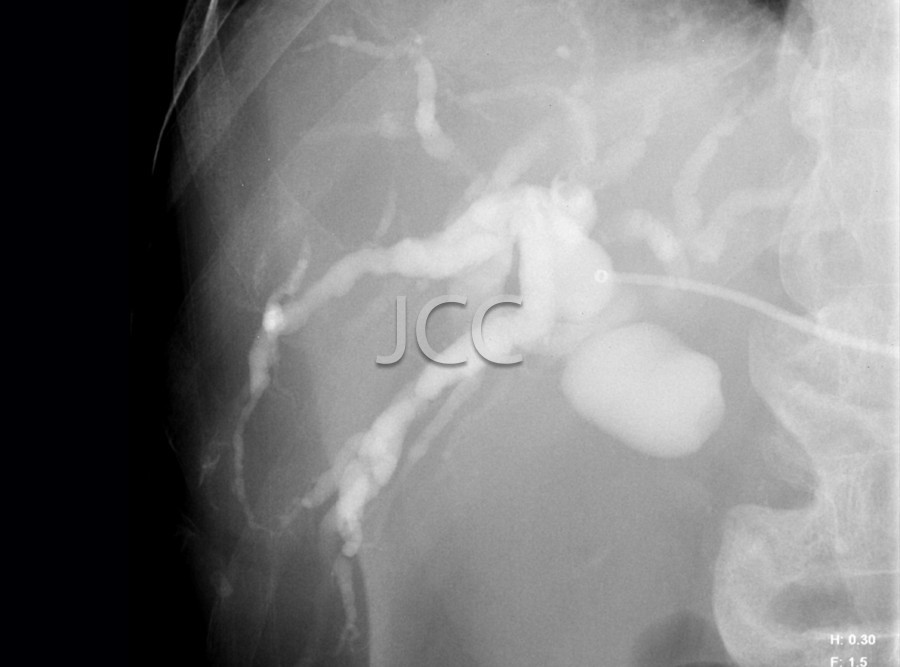

Radiologia de Intervenção - Drenagem Biliar

• O Paciente deverá estar em jejum 4 horas.